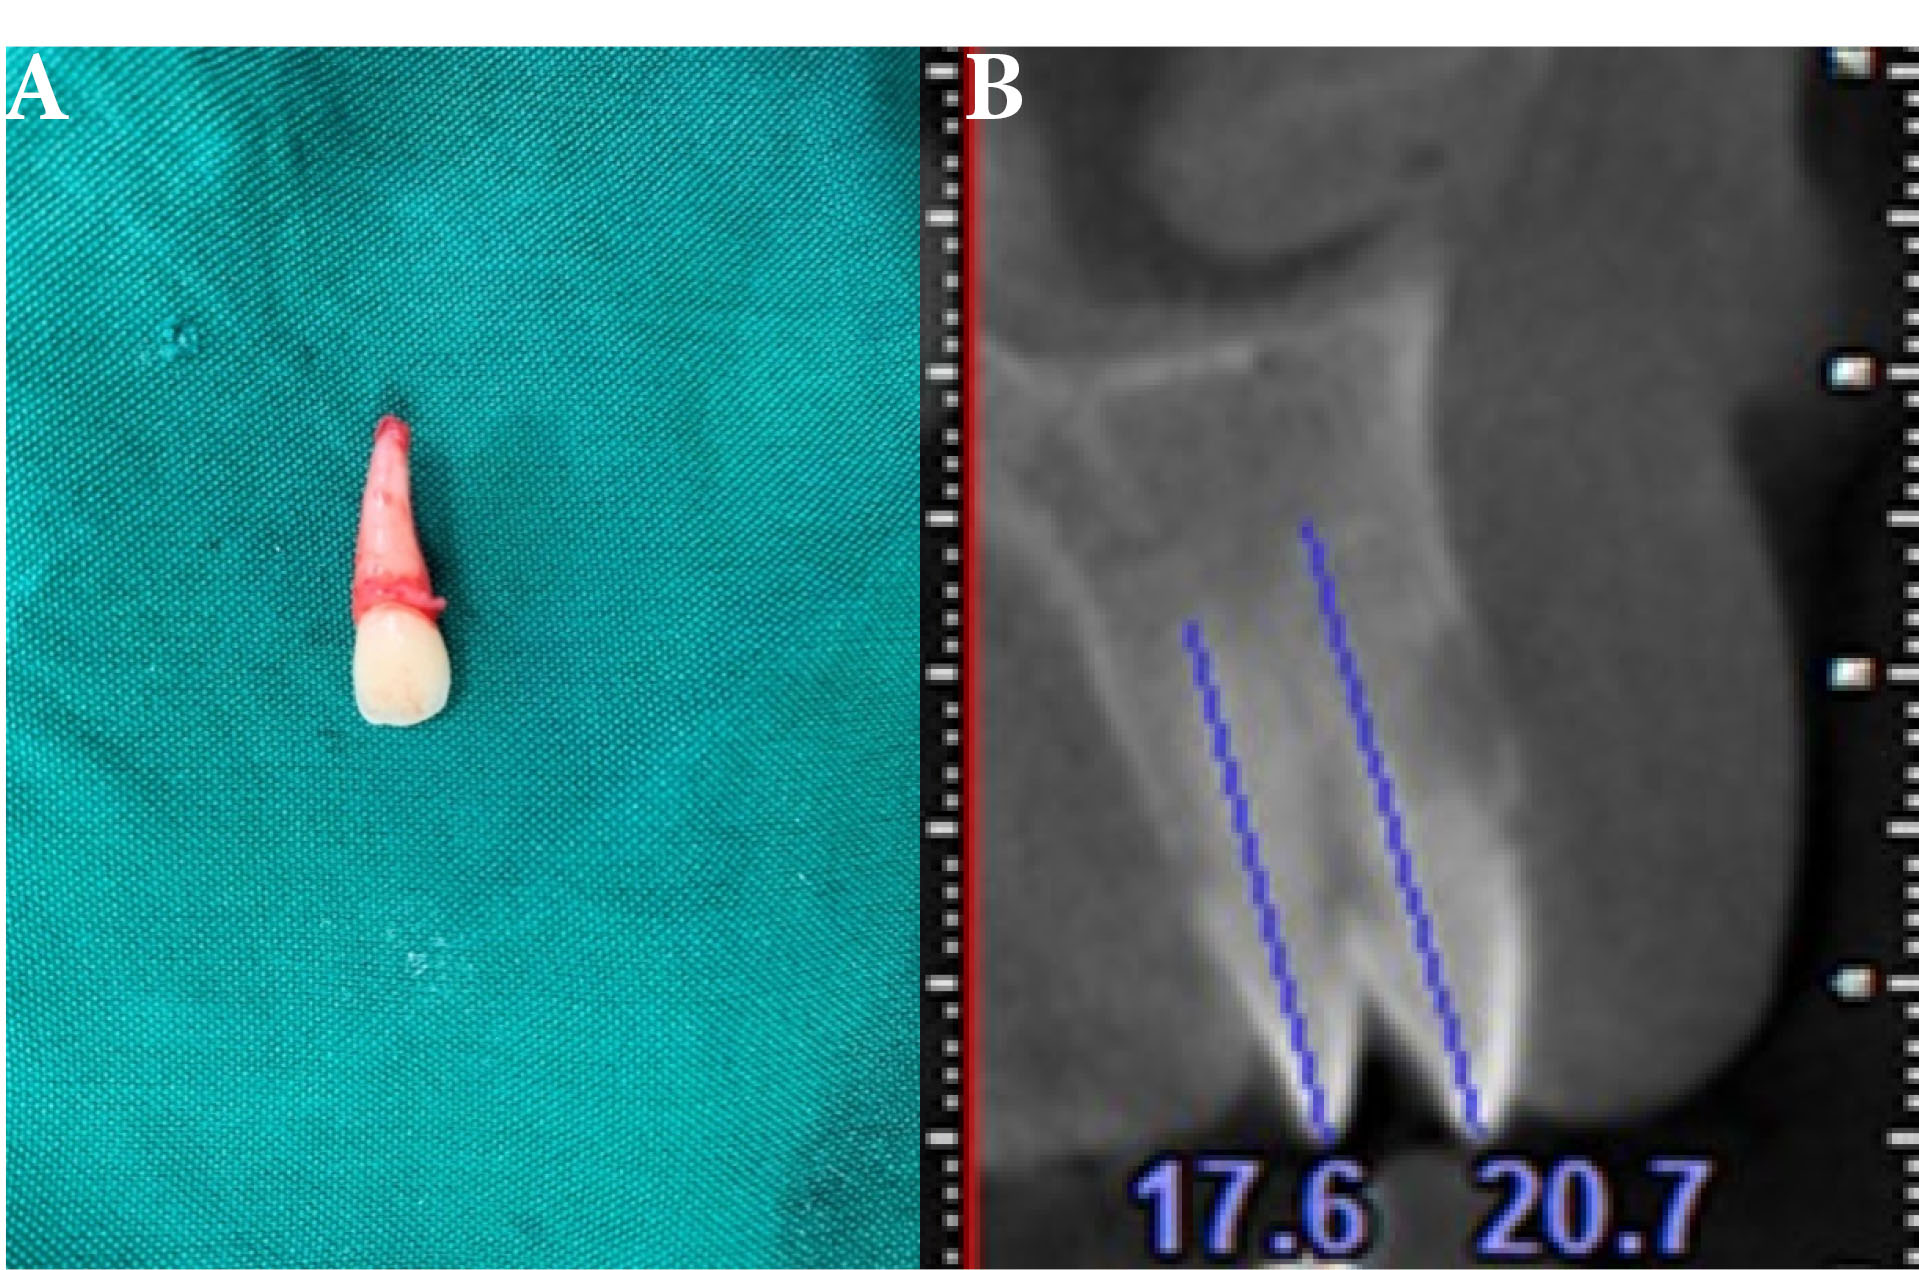

The patient was in good systemic conditions according to the history given by her parents, and she was referred to pediatric endocrinologist for hormone testing for further investigations and possible systemic issues due to her irregular eruption sequence. In serum and urine, thyroid stimulating hormone, PTH, calcium, phosphorous and glucose were tested but nothing abnormal was seen in the tests. Dental panoramic radiograph and cone-beam computed tomography (CBCT) were suggested for a more comprehensive examination of the patient’s condition (Figure 4). CBCT axial cut (Figure 5B) showed that due to its short tooth length (17.6 mm) (Figure 3) and its improper location, the extra lateral tooth that was palatally located was extracted. Preventive resin restoration was also performed for deep fissure and initial caries on first permanent molars. As parents were not aware of the condition of the early eruption and believed that their molars were deciduous teeth, the patient was scheduled to have regular follow-ups. The decision for publishing patient data was taken after receiving an informed consent from her parents.

ajdr-13-72-g005

Figure 5.

Supernumerary Teeth. (A) Extraction of supernumerary teeth. (B) CBCT axial cut.